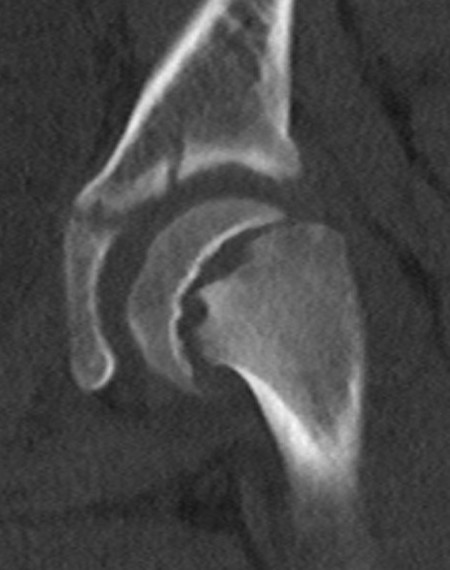

Lateral xray

Mild and moderate SCFE on left hips